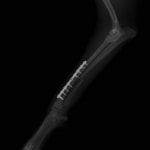

症例3:キルシュナーワイヤーのピンニングによる整復

ペルシャ猫 11ヶ月齢 雄

他院にて左大腿骨遠位の成長板骨折(salter-harrisⅠ型)が認められており、治療相談を目的として来院。当院にて、キルシュナーワイヤーを用いたピンニングにより骨折部位の整復を行いました。術後の経過は良好で、現在も経過観察中です。

術前レントゲン

術後レントゲン